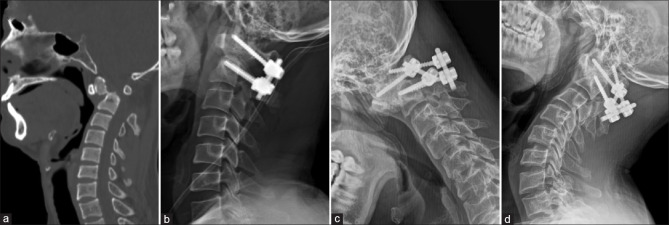

Introduction: The options for the management of type II odontoid fractures in young patients include anterior screw fixation, posterior spinal fusion, or halo-vest immobilization (HVI). However, there is a recent trend away from nonoperative management and an increase in primary operative stabilization across several centers. Hence, our study aims to compare the functional and radiological outcomes of type II odontoid fractures in young patients managed with HVI and surgery.

Materials and methods: A retrospective analysis of 70 patients with type II odontoid fracture who were managed in our institution with a mean age of 47 years was included in our study. The clinical details included the Neck Disability Index (NDI), Visual Analog Scale (VAS) for neck pain, and S-Range of Movement (ROM)-Neck score. Radiological details included union status, atlanto-dens interval, amount of displacement and angulation, and transverse ligament injury. Both the clinical and radiological parameters were compared between the patients who underwent HVI (n = 28) and surgery (n = 42).